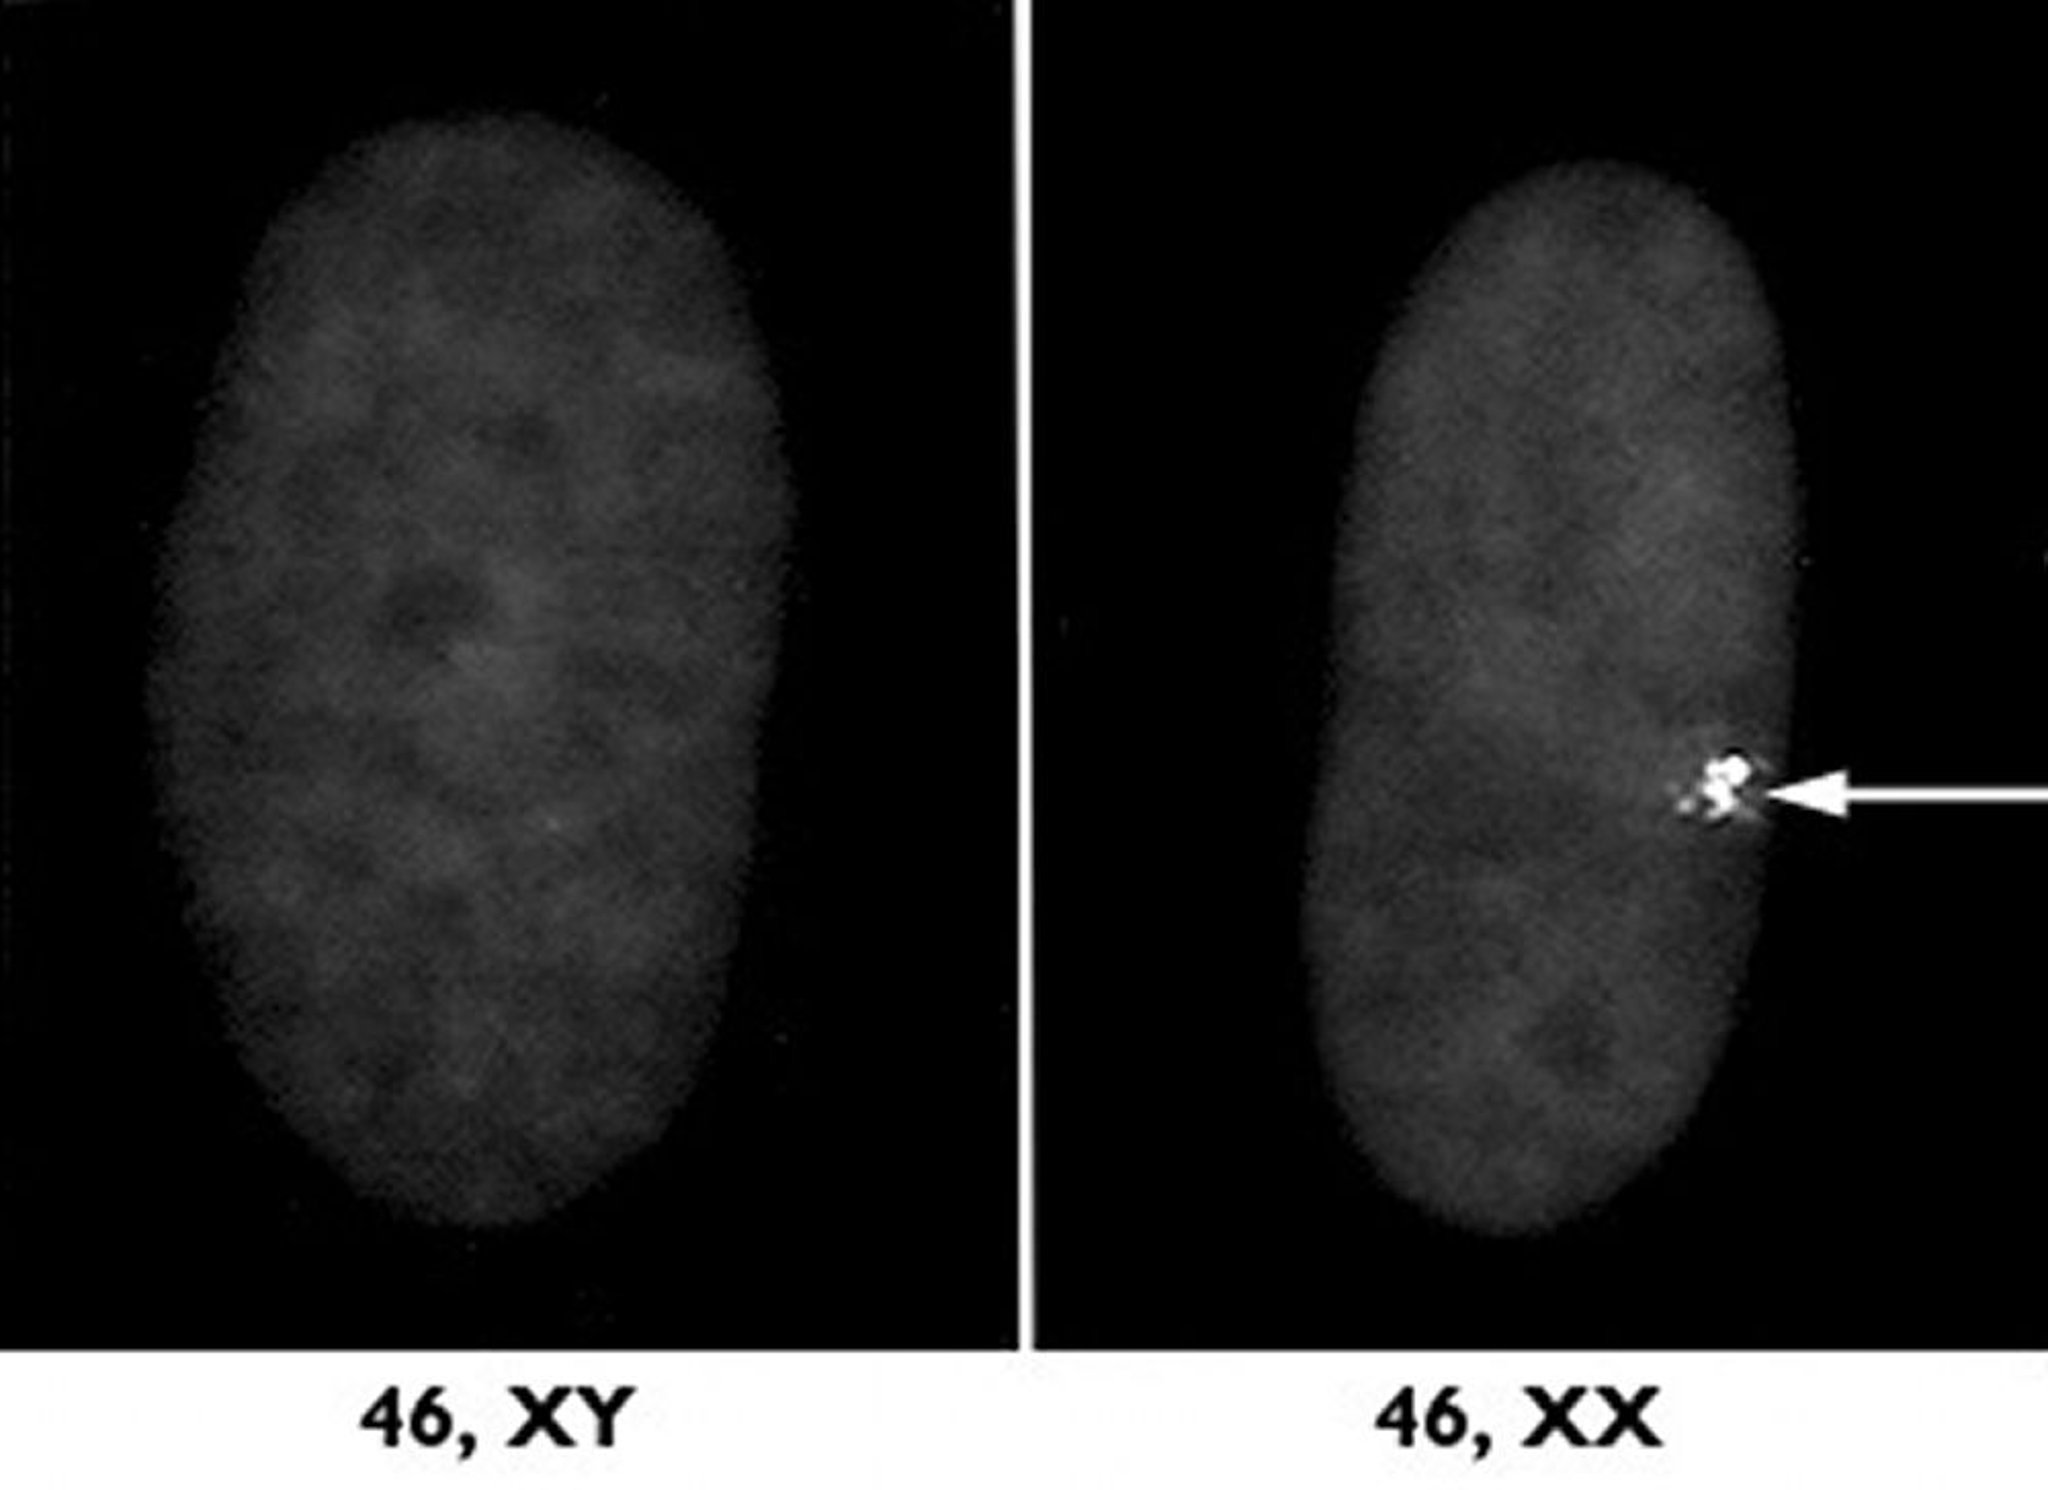

Cromosoma X inactivo

Uno de los dos cromosomas X de las mujeres se desactiva mediante un proceso llamado inactivación del cromosoma X. A la derecha se observa este cromosoma X inactivo como un bulto denso (flecha) en una muestra microscópica de un núcleo celular de una mujer. A la izquierda se puede observar una muestra de un varón para su comparación.

Cortesía de los Drs. L. Carrell y H. Williard, Case Western Reserve University School of Medicine.